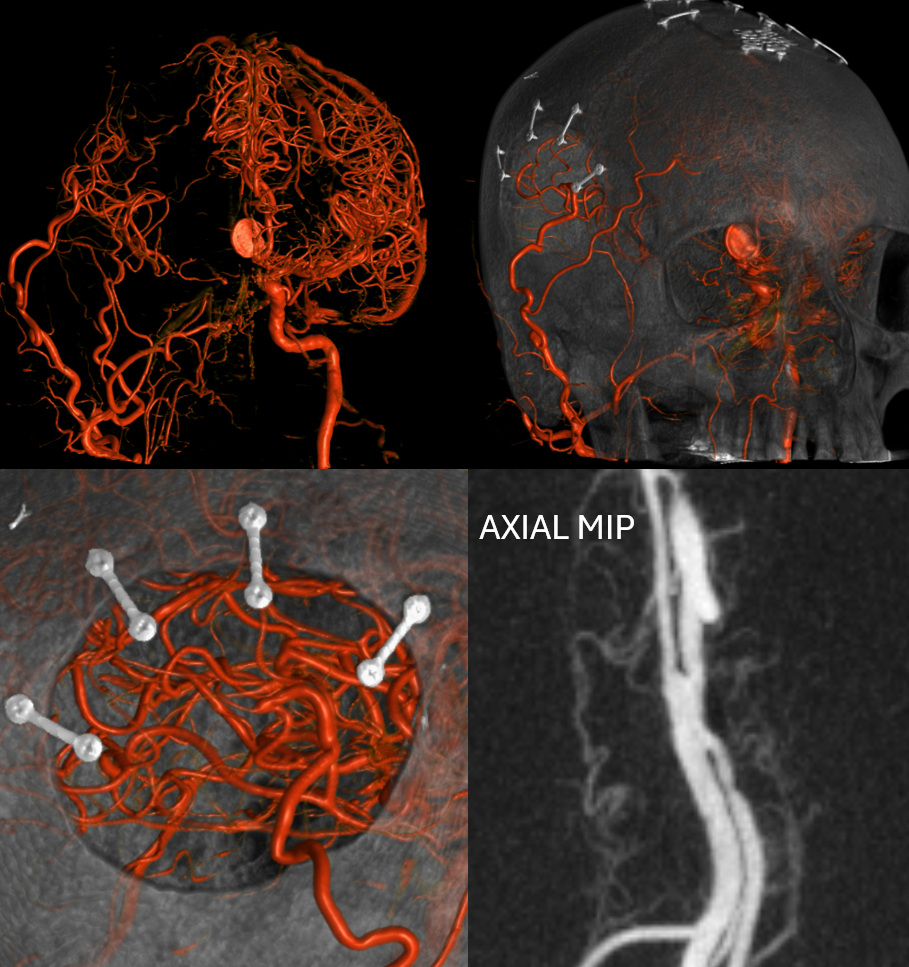

Giant ACOM

More problems? Yes

So far, we have a giant mostly thrombosed ACOM aneurysm with adjacent edema, a chronically occluded right cervical ICA, and right ACA dependent on the ACOM flow… Not easy

Spins are good

A secondary reconstruction and detailed analysis is better. What does arrow point to?

Spin

A better unsubtracted spin